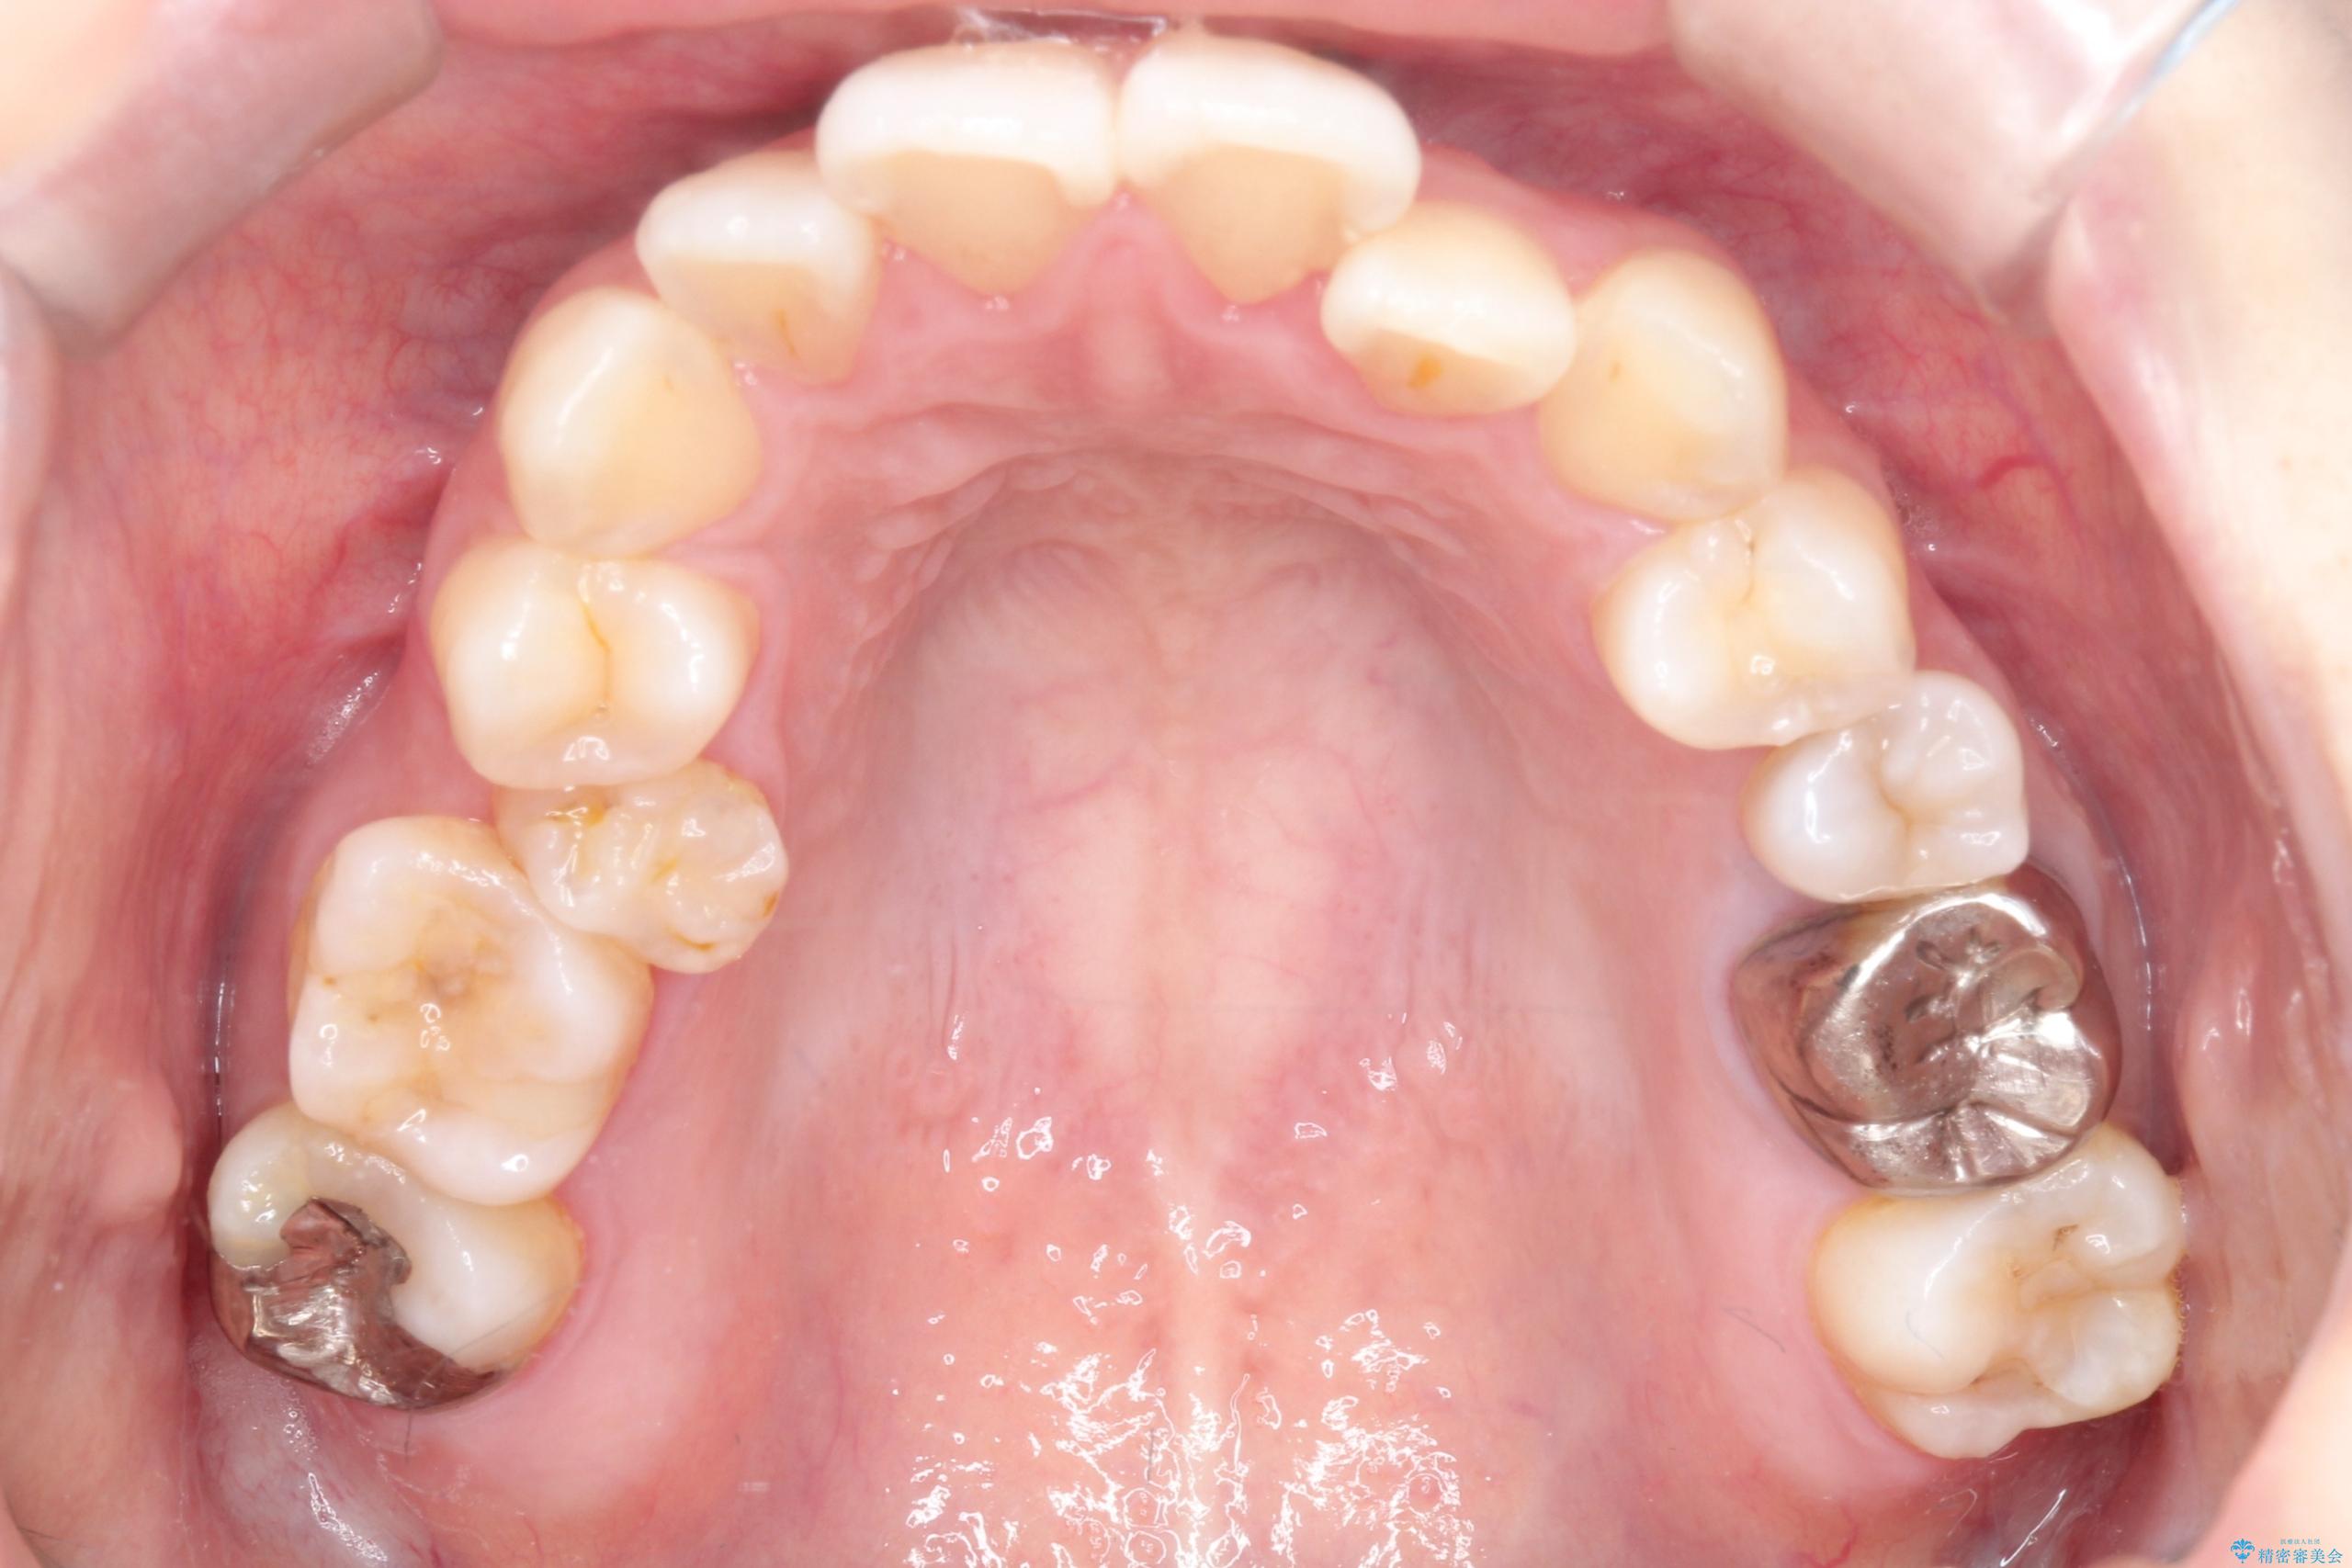

- 主訴:口元を下げて前突感を無くしたい、下の歯の凹凸も無くしたい

右側第二小臼歯、左側第一小臼歯、下顎両側第一大臼歯を抜歯しワイヤ-矯正を行いました。

骨格的顎の変位を認めたため、顔貌に対しピッタリ上下の歯の正中を合わせることは難しいと説明し、上下左右計4本小臼歯を抜歯しワイヤー矯正治療を行いました。